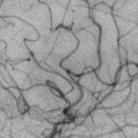

The rapid and accurate direct multi-frame interpolation method for Digital Subtraction Angiography (DSA) images is crucial for reducing radiation and providing real-time assistance to physicians for precise diagnostics and treatment. DSA images contain complex vascular structures and various motions. Applying natural scene Video Frame Interpolation (VFI) methods results in motion artifacts, structural dissipation, and blurriness. Recently, MoSt-DSA has specifically addressed these issues for the first time and achieved SOTA results. However, MoSt-DSA's focus on real-time performance leads to insufficient suppression of high-frequency noise and incomplete filtering of low-frequency noise in the generated images. To address these issues within the same computational time scale, we propose GaraMoSt. Specifically, we optimize the network pipeline with a parallel design and propose a module named MG-MSFE. MG-MSFE extracts frame-relative motion and structural features at various granularities in a fully convolutional parallel manner and supports independent, flexible adjustment of context-aware granularity at different scales, thus enhancing computational efficiency and accuracy. Extensive experiments demonstrate that GaraMoSt achieves the SOTA performance in accuracy, robustness, visual effects, and noise suppression, comprehensively surpassing MoSt-DSA and other natural scene VFI methods. The code and models are available at https://github.com/ZyoungXu/GaraMoSt.